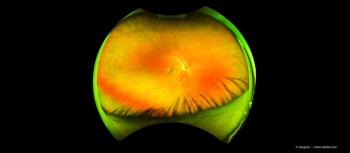

Treatments continue to evolve, and glaucoma treatments are no different. When treating glaucoma patients, it is important to stay up to date on new technologies and continue to monitor IOP.

The next patient sitting in your chair may have narrow angles. Find out how to best diagnose and manage patients with narrow angles; it can have a significant long-term impact on their visual outcome.

Evolving procedures continue to change the landscape of glaucoma treatments. Chief Optometric Editor Benjamin P. Casella, OD, FAAO, explores how the use of minimally (or micro-) invasive glaucoma surgery (MIGS) techniques can increase positive outcomes when treating glaucoma patients.